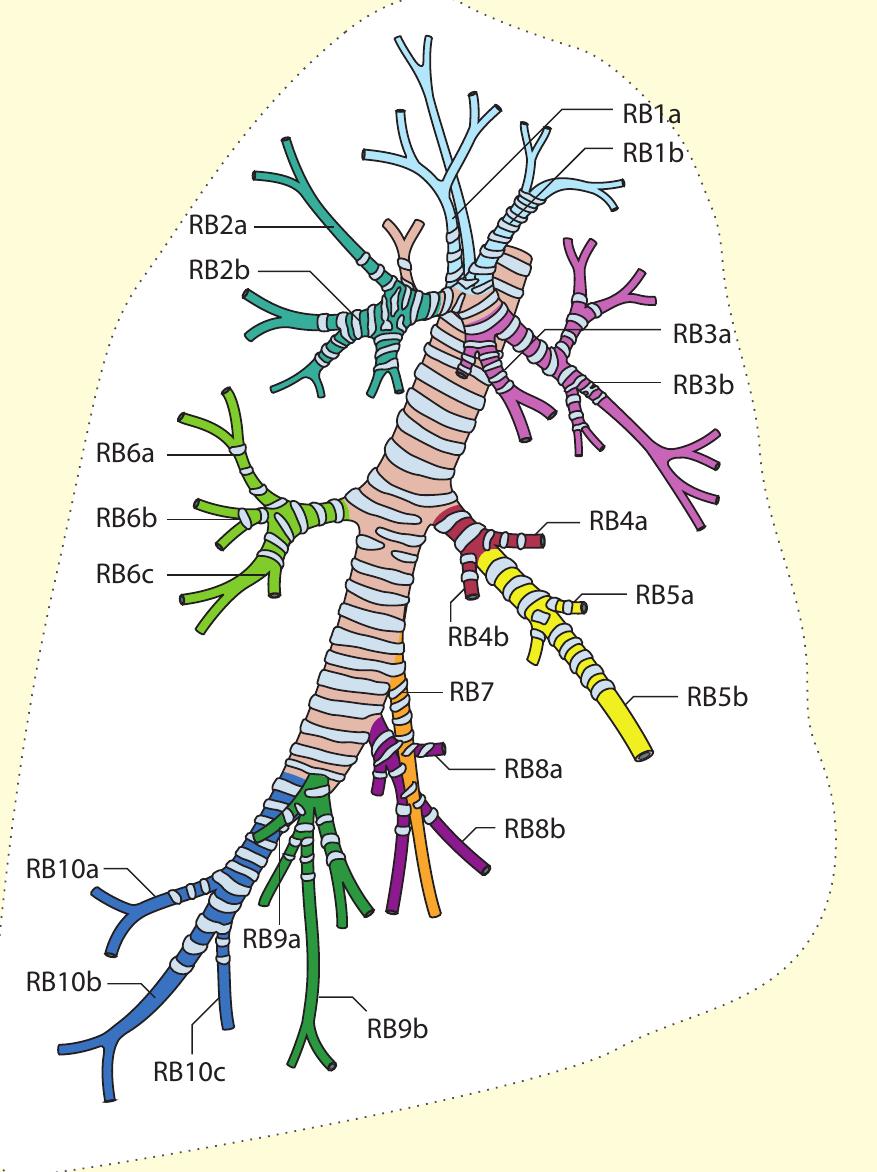

- The bronchoscope is then rotated anticlockwise by 150° to examine the subcarinal lymph nodes (station 7), extending down to the distal margin of the bronchus intermedius.

- Superior to the 11R lymph node, the right upper lobe bronchus and pulmonary artery may be visible.

- Our approach, for example, for the right lower lobe is to treat RB10 (right posterior basal bronchus) first, using the BF260 bronchoscope (external diameter 4.3 mm) so that the distal subsegments can be assessed.